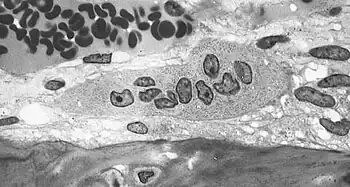

The underlying mechanism in all cases of osteoporosis is an imbalance between bone resorption and bone formation.[103][104] In normal bone, matrix remodeling of bone is constant; up to 10% of all bone mass may be undergoing remodeling at any point in time. The process takes place in bone multicellular units (BMUs) as first described by Frost & Thomas in 1963.[105] Osteoclasts are assisted by transcription factor PU.1 to degrade the bone matrix, while osteoblasts rebuild the bone matrix. Low bone mass density can then occur when osteoclasts are degrading the bone matrix faster than the osteoblasts are rebuilding the bone.[103][106]

The activation of osteoclasts is regulated by various molecular signals, of which RANKL (receptor activator of nuclear factor kappa-B ligand) is one of the best-studied.[104] This molecule is produced by osteoblasts and other cells (e.g., lymphocytes), and stimulates RANK (receptor activator of nuclear factor κB). Osteoprotegerin (OPG) binds RANKL before it has an opportunity to bind to RANK, and hence suppresses its ability to increase bone resorption. RANKL, RANK, and OPG are closely related to tumor necrosis factor and its receptors. The role of the Wnt signaling pathway is recognized, but less well understood. Local production of eicosanoids and interleukins is thought to participate in the regulation of bone turnover, and excess or reduced production of these mediators may underlie the development of osteoporosis.[37] Osteoclast maturation and activity is also regulated by activation of colony stimulating factor 1 receptor (CSF1R).[108] Menopause-associated increase production of TNF-α stimulates stromal cells to produce colony stimulating factor 1 (CSF-1) which activates CSF1R and stimulates osteoclasts to reabsorb bone.[109]

Trabecular bone (or cancellous bone) is the sponge-like bone in the ends of long bones and vertebrae. Cortical bone is the hard outer shell of bones and the middle of long bones. Because osteoblasts and osteoclasts inhabit the surface of bones, trabecular bone is more active and is more subject to bone turnover and remodeling. Not only is bone density decreased, but the microarchitecture of bone is also disrupted. The weaker spicules of trabecular bone break ("microcracks") and are replaced by weaker bone. Common osteoporotic fracture sites, the wrist, the hip, and the spine, have a relatively high trabecular bone to cortical bone ratio. These areas rely on the trabecular bone for strength, so the intense remodeling causes these areas to degenerate most when the remodeling is imbalanced. Around the ages of 30–35, cancellous or trabecular bone loss begins. Women may lose as much as 50%, while men lose about 30%.[39]

Light micrograph of an osteoclast displaying typical distinguishing characteristics: a large cell with multiple nuclei and a "foamy" cytosol.

Light micrograph of an osteoclast displaying typical distinguishing characteristics: a large cell with multiple nuclei and a "foamy" cytosol. -

Light micrograph of osteoblasts, several displaying a prominent Golgi apparatus, actively synthesizing osteoid containing two osteocytes.

Light micrograph of osteoblasts, several displaying a prominent Golgi apparatus, actively synthesizing osteoid containing two osteocytes. -